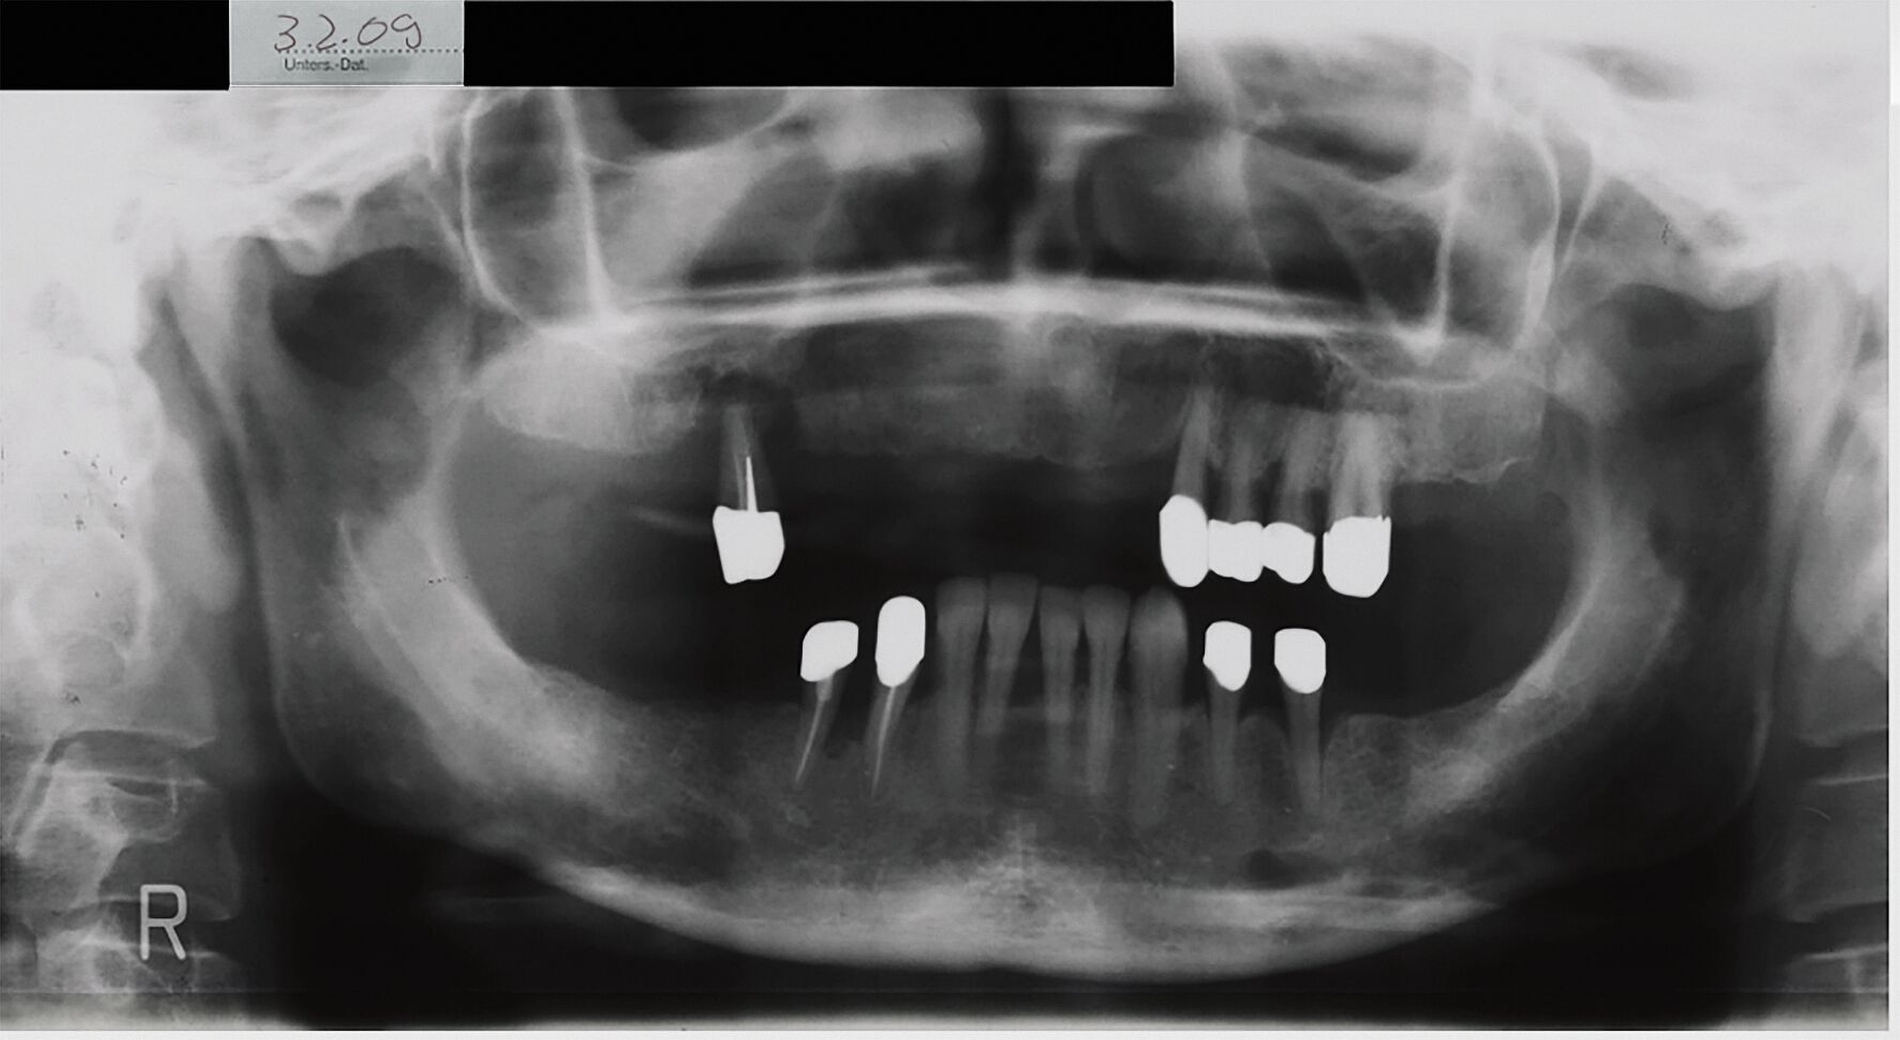

Die DVT bestätigte den Befund in der PSA. Die dreidimensionale digitale Darstellung zeigte einen Verlauf des Nervus alveolaris inferior links durch die fragliche Osteolyse. Auf einer vor zehn Jahren alio loco angefertigten PSA war der suspekte Befund auch schon sichtbar gewesen, jedoch mit deutlich geringerem Volumen.

Die Raumforderung im Bereich des Foramen mentale links wies im Vergleich zur PSA aus 2009 eine deutliche Progredienz auf. Aus diesem Grund wurde trotz des Risikos der Schädigung des Nervus alveolaris inferior die Indikation zur operativen Exploration und Probeentnahme zur Diagnosesicherung gestellt. Differenzialdiagnostisch lässt sich solch ein osteolytischer Prozess neben einer vaskulären Läsion gleichermaßen mit einer zystischen Läsion, einem unizystischen Ameloblastom, einer aneurysmatischen oder solitären Knochenzyste, einem Myxom oder einem Schwannom vereinbaren. Ein malignes Geschehen ist aufgrund des radiologischen Phänotyps unwahrscheinlich, jedoch nur durch histologische Abklärung sicher auszuschließen. Diese ergab postoperativ die Primärdiagnose eines kavernösen Hämangioms.